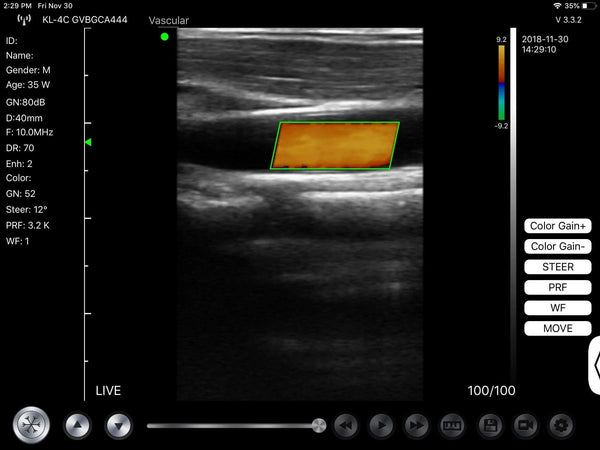

Vascular

Wireless Ultrasound Probe Used in Vascular

Wireless handheld ultrasound are quickly and clearly visualise and assess patient central and peripheral veins, high-definition imaging to guide and perform safe vascular access procedures and complete nursing procedures

Handheld ultrasound plays an important role in Vascular:

• Central venous assessment and puncture, arterial assessment,

• varicose vein treatment,

• stroke screening (vascular ultrasound),

• peripheral venous assessment and puncture,

• peripheral arterial puncture,

• prosthesis placement,

• carotid atherosclerosis.